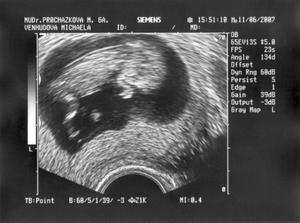

Pohádkovou svatbu jsme měli 14.10.2006, manželovi bylo 33 a mně 20, letos v lednu mne chytly příšerné nezadržitelné mateřské pudy, vysadila jsem HA a koncem března se nám podařilo otěhotnět. Náš mimoušek by se měl narodit 25.12.2007, zatím mu říkáme Mišátko, tatínek říká mamince Mišánek, tak mimiko je Mišátko.